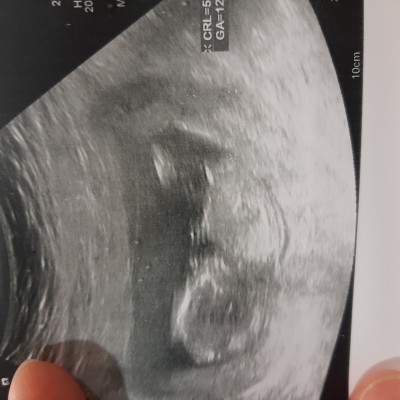

Cinsiyet tahmini yapabilecek olan var mı?

image